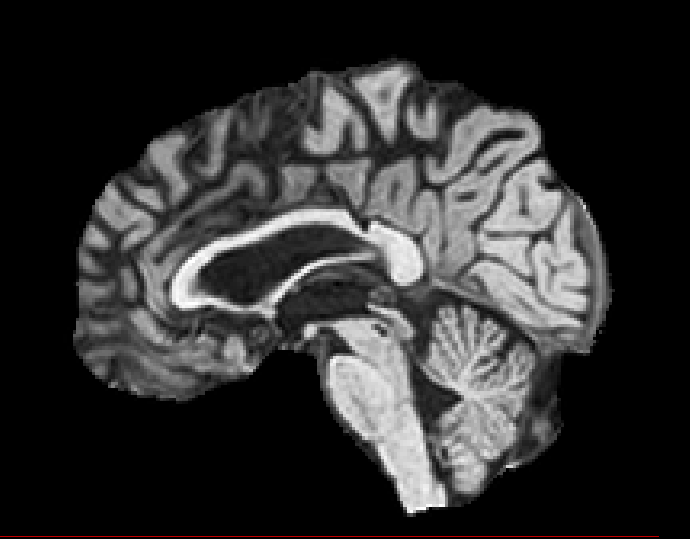

Exp. 1: Segmented adult brain data is used to evaluate our network’s regression performance with known ground truth . 85 brains from the ADNI data set[1] were randomly selected; 70 brains for and 15 brains for . Fig. 2 shows an example slice of the ground truth and the reconstructed .

Reconstructing from initialisation without SVR yields a PSNR of 23.7 1.09; with subsequent SVR the PSNR increases to 29.52.43 when tested on 15 randomly selected test volumes after four iterations of SVR.

Here we show for Exp. 1, Exp. 2, and Exp. 3 randomly selected examples of images that have been presented to the network (ground truth) compared to an image sampled at the predicted location.

In these experiments, we present a ground truth (GT) image to the network to estimate the respective transformation parameters needed to reorient the slice in its correct world co-ordinates. Using the transformation parameters, we generated a slice from the 3D atlas in the location where the network has predicted that slice should be (denoted as SVRNet).

The slices are compared side-by-side to give a visual representation of “where the slice really is” and “where the network thinks the slice is”.

0..5.1 Exp. 1:

Slices, extracted from a correctly registered and reconstructed 3D volume, from the testing data set are presented to the network. The predicted slice is extracted from the same volume, using parameters estimated by SVRNet as shown in Fig. 8 and 9.